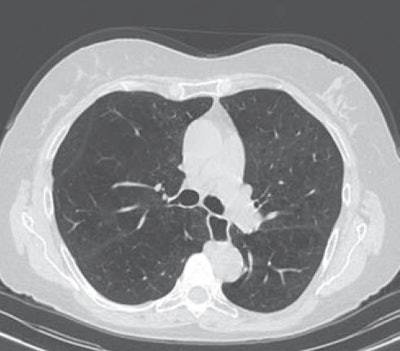

An artificial intelligence (AI) algorithm can provide fully automated quantification of emphysema, offering potential as a tool for image-based diagnosis and quantification of emphysema severity, according to research published online on 4 March in the American Journal of Roentgenology.

To see if AI could accurately quantify emphysema, the researchers used a deep image-to-image network -- a multilayer convolutional neural network that had been trained and tested on more than 10,000 CT datasets acquired on scanners from three vendors at over 20 clinical sites in the U.S. and Europe. Approximately 25% of these datasets were from patients with emphysema.

To determine if reconstruction methods would impact performance, the researchers applied the algorithm to two reconstruction kernels. The first method used a section thickness of 1.5 mm with a long kernel, while the second utilized a section thickness of 1.5 mm with a soft-tissue kernel. Emphysema was quantified using spatial filtering and a threshold of -950 Hounsfield units.